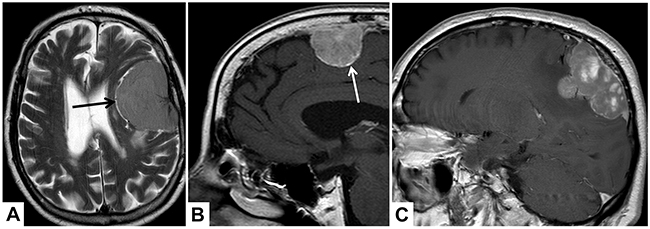

Patients were included in case of available sufficient preoperative MRI, defined as available axial T1 contrast-enhanced images. Preoperative MRI was analyzed by a team of two radiologists (PBS and AA) blinded to any histopathological data and disagreement was dissolved through discussion. Tumour location was dichotomously classified as “convexity or falx/parasagittal” and “other locations”. Tumour and edema volumes (VT and VE) were estimated using the established formula for a spheroid V=4/3 × π × r1 × r2 × r3, where “r” is the tumour radius at the site of its largest extension in axial (r1), coronal (r2) and sagittal (r3) planes [7]. According to previous studies investigating assocations between MRI and WHO grade or patient’s prognosis, the following radiological variables were investigated (see illustrative MRI examples in Figure 3): Integrity of the arachnoid layer was analyzed on T2 imaging and was diagnosed as intact in case of a sharp tumour border and/or evidence of cerebrospinal fluid at the brain/meningioma surface [13]. Capsular enhancement and tumour shape were evaluated on gadolinium-enhanced T1-weighted imaging and dichotomously registered as absent/present and regular or irregular, respectively [12, 13]. Similarly, pattern of contrast enhancement was registered as heterogeneous or homogenous on T1-weighted images [13]. Intensity of the tumour and presence of intratumoural calcifications were analyzed on T2 images and classified as hyper-, iso- or hypointense as compared to the grey matter and present or absent, respectively [12].

Figure 3: Illustrative examples of the analyzed MRI variables. In (A), axial T2-weighted MRI shows cerebrospinal fluid at the brain/meningioma border (arrow), indicating a distinct tumour surface with an intact arachnoid layer. In (B and C), sagittal T1-weighted images show a contrast-enhancing tumour capsule (B, arrow), a heterogeneous gadolinium enhancement (C) and an irregular tumour shape with mushroom-like growth (C).